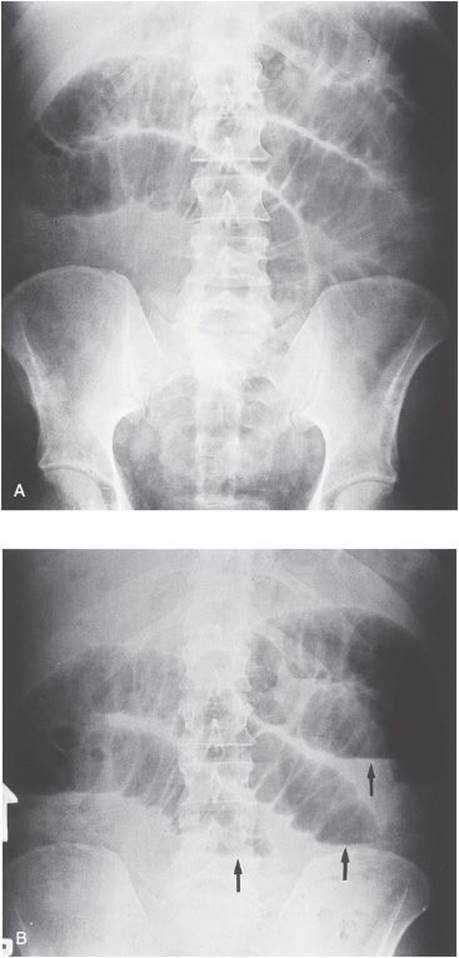

Radiological examination should include an upright chest x-ray to rule out free air as well as supine and upright abdominal films (aka KUB) to look for air–fluid levels and dilated loops of bowel (see Figure 14-1A and B).

Figure 14-1. (A) Supine KUBs with dilated loops of small bowel. (Reproduced with permission from Zinner MJ, Ashley SW. Maingot’s Abdominal Operations. 11th ed. New York: McGraw-Hill; 2007 [Figure 17-9].) (B) Upright KUB with multiple air–fluid levels (arrows). (Reproduced with permission from Zinner MJ, Ashley SW. Maingot’s Abdominal Operations. 11th ed. New York: McGraw-Hill; 2007 [Figure 17-9].)